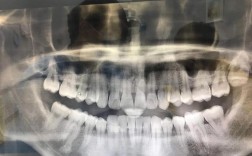

- 面诊是关键: 价格只是考虑因素之一。务必选择至少2-3家不同类型(公立、连锁、口碑好的私立)的机构进行面诊咨询。 医生需要亲自检查你的牙齿情况,拍X光片(全景片、头颅侧位片等),才能给出个性化的矫正方案和准确的报价。